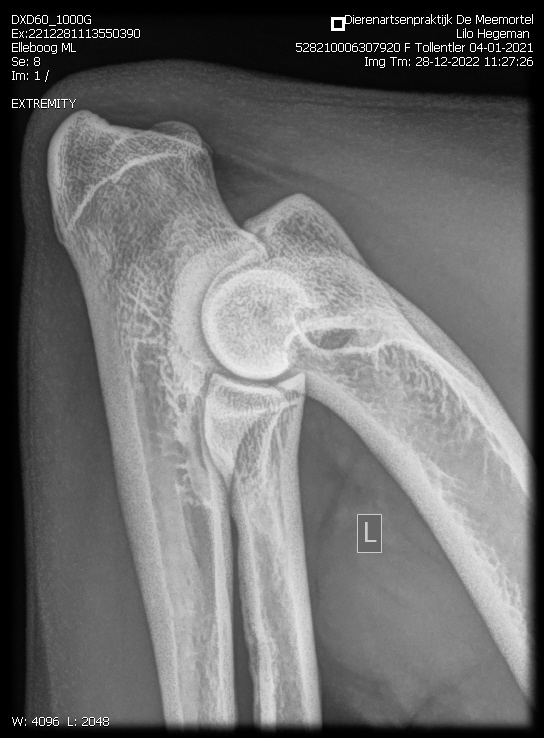

Eerste Gezondheidsresltaten Tollentler

Lilo onze eerstgeborene Tollentler in de kleur Tan is inmiddels volledig getest.

Zo ook het overige. Zie onderstaand.